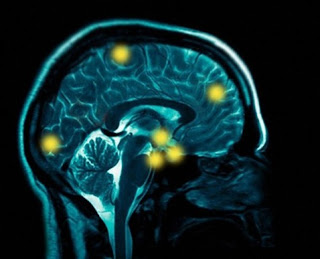

- Los científicos estudiaron a los hombres sin antecedentes de trastornos psiquiátricos o dependencia de sustancias. Los hombres completaron un cuestionario que permitió evaluar diferentes aspectos de la impulsividad. Se sometieron a una espectroscopía, por resonancia magnética especializada, una técnica que permite la medición de la cantidad de GABA en pequeñas regiones del cerebro.

- El equipo de investigación que los hombres con más neurotransmisor GABA en el córtex prefontral dorsolateral tenían menos tendencia a la impulsividad, el llamado sentimiento de urgencia, la tendencia a actuar de forma precipitadamente en respuesta a la angustia y otras emociones fuertes.